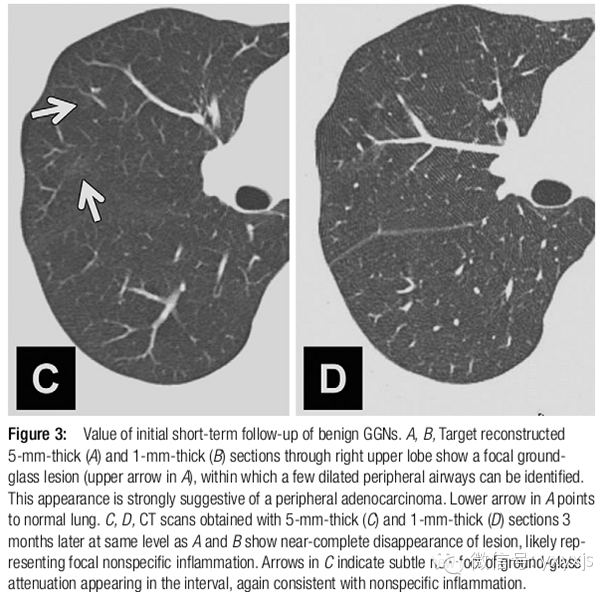

2 孤立的、直径大于5mm的纯GGO,3月后复查,以观察病变是否消失。如持续存在,则每年复查,至少持续3年。

病理上为AAH、原位腺癌和一少部分微浸润腺癌。不建议使用抗生素。PET检查价值不大。CT引导穿刺不推荐,阳性率较低。